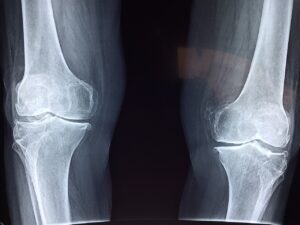

Zioło ma liczne korzyści, takie jak promowanie zdrowia kości, pobudzanie układu odpornościowego, wspieranie metabolizmu, działanie jako środek antybakteryjny, powodowanie efektów moczopędnych i odwadniających, zmniejszanie stanów zapalnych, wykazywanie właściwości przeciwgrzybicznych, wypłukiwanie „piasku” z dróg moczowych i stawów, łagodzenie bólu stawów i mięśni, eliminowanie kaszlu i flegmy, wzmacnianie zdrowia skóry i gojenia się ran oraz uspokajanie układu nerwowego.

- zmniejszanie bólu w stawach i czasu trwania choroby